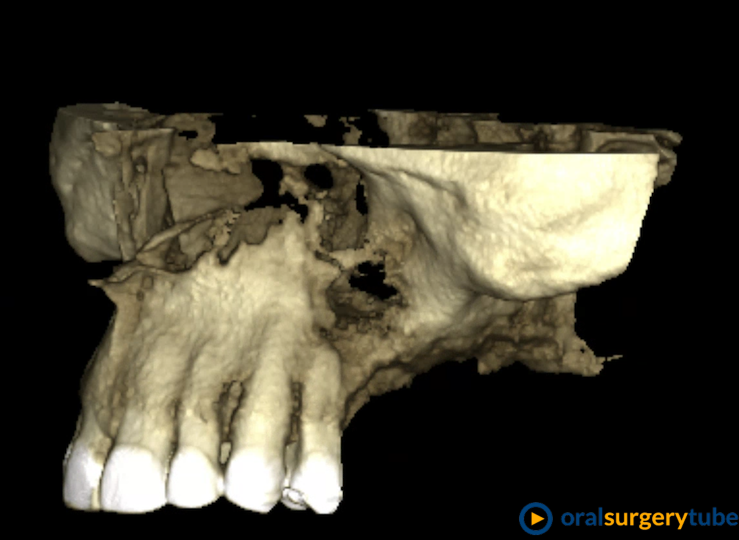

REGENERACIÓN OSEA DEL CUADRANTE 2

Buenos dias, queria regenerar con altura y anchura el cuadrante dos.